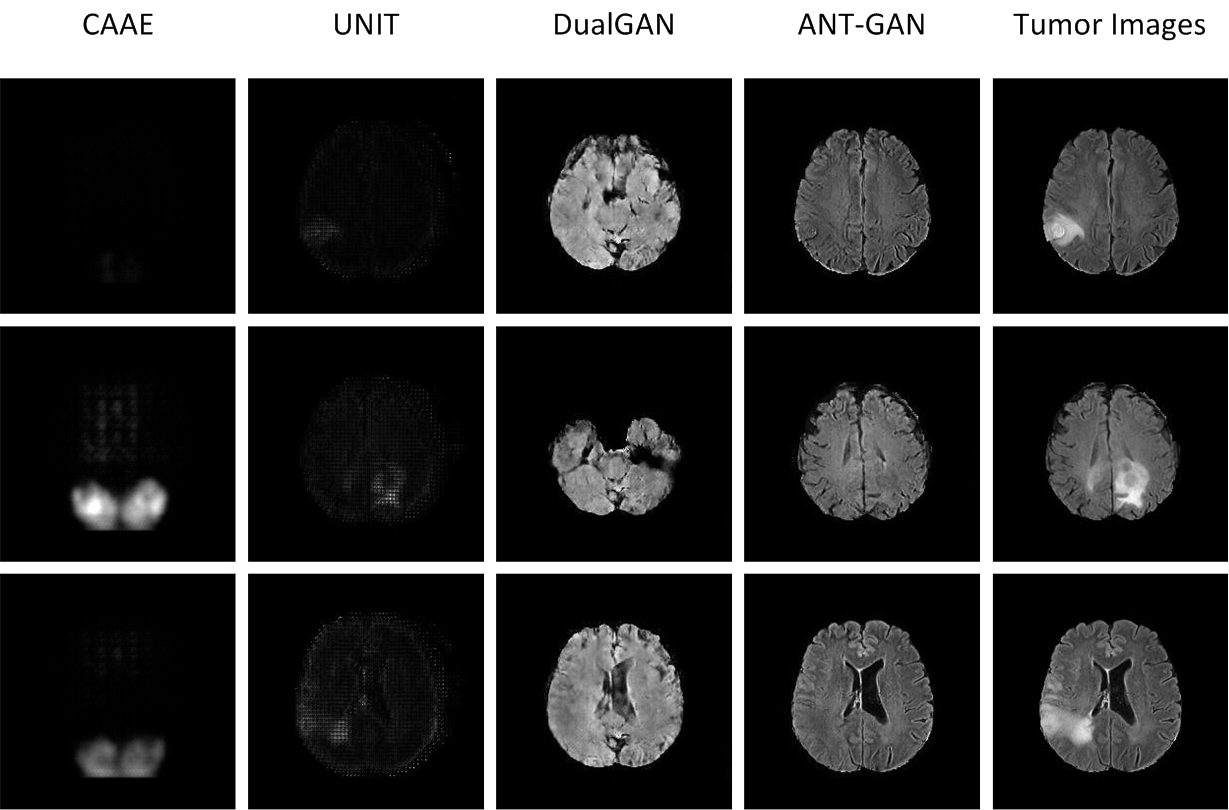

IV-B3 Comparison with other GAN formulations

We compare the proposed ANT-GAN model with the prior work using constrained adversarial auto-encoder model (CAAE) for lesion detection [6] and other two recently proposed state-of-the-art unsupervised GAN models, UNIT [19] and DualGAN [32]. We show these results in Figure 7. We observe that UNIT does not work for this problem. The data sets in this case are too small and the images too large for these models to learn in their less-regularized settings. ANT-GAN also outperforms DualGAN in imaging quality. While DualGAN uses cycle consistency, which makes learning 𝒢𝒢\mathcal{G} easier with less data, no shortcut in 𝒢𝒢\mathcal{G} is used by DualGAN, unlike ANT-GAN. Finally, the stricter regularization of the anomaly mask in ANT-GAN (absent from all other GAN models) not only can enforce greater fidelity to the original image, which is required for this problem, but also aid GAN learning by introducing greater supervision. We observe that CAAE struggles to produce high quality normal-looking medical images in such a high-resolution image synthesis task, which is also the main limitation mentioned in that paper, where evaluations are performed on much smaller images of size 32×32323232\times 32.

Refer to caption

Figure 7: We compare ANT-GAN with other state-of-the-art GAN methods less tailored to this problem.